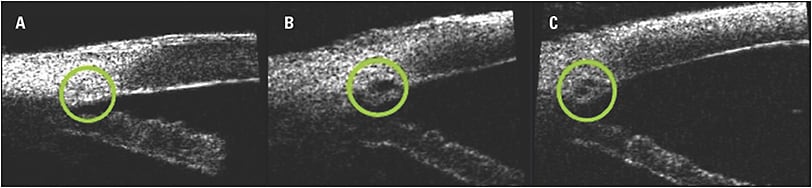

Modification of these abnormalities has been a target of therapy for decades, both surgically and medically. In the 1980s, pioneers like Robert Stegmann, MD, found that by viscodilating Schlemm’s canal via viscocanalostomy, patency can be regained and pressure effectively lowered.10 Viscocanalostomy has been shown to be quite effective, but canal dilation is limited to a few clock hours distal and lateral to the site of treatment. In the early 2000s, iScience developed the iTrack catheter, which is the world’s smallest fiberoptic microcatheter, and this allowed for the entire canal to be circumnavigated and viscodilated, a procedure now known as canaloplasty. Work by these pioneers showed that the forceful injection of viscoelastic into the canal using the iTrack catheter (now owned by Ellex) helped modify some of the above-mentioned pathologic changes by evaluating cadaveric eyes with electron microscopy and in vivo using high definition ultrasonography. Trabecular lamellae separated, microperforations in the inner wall were created, the canal diameter and collector channels were greatly dilated (Figure 1), and previously stenotic canals were transformed into conduits of flow.